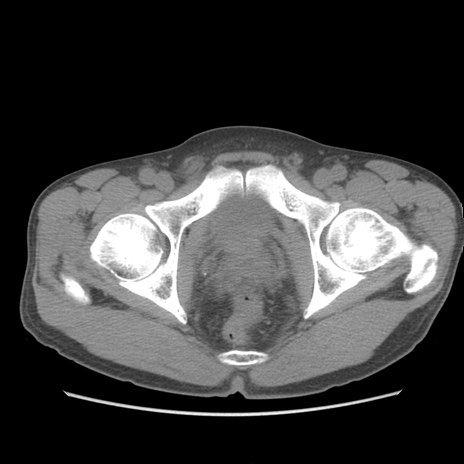

症例56 CT(横断像)

脂肪ウインドウ